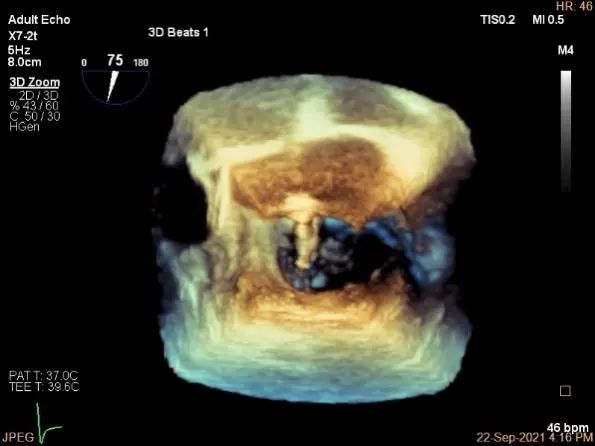

三维评估两个夹子位置

3D-color再次确定未见残余分流

评估瓣口条件,平均跨瓣压差:4mmHg

肺静脉血流频谱恢复正常